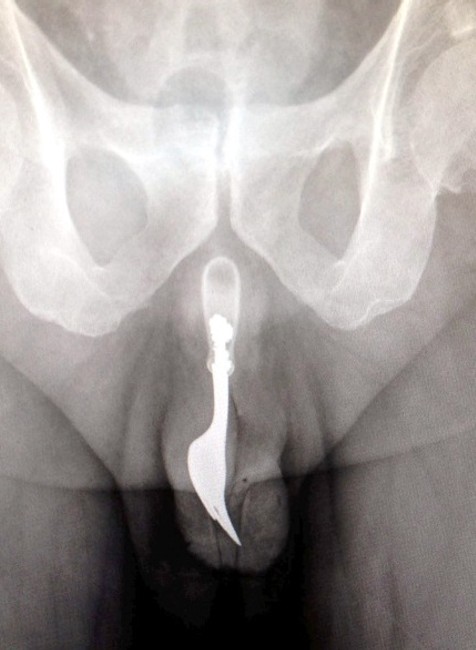

FOTO. Dôchodcovi našli v penise 10-centimetrovú vidličku!

CANBERRA / Keď lekári prijali na pohotovosti v Austrálii staršieho pacienta, ktorý sa sťažoval na krvácanie z pohlavného orgánu, to ešte netušili, čo mu v ňom nájdu. Rontgenová snímka ich musela šokovať! V penise mal totiž strčenú 10 cm dlhú, oceľovú kuchynskú vidličku! A pravda o tom, ako sa mu tam dostala, nenechala na seba dlho čakať...

Lekári z austrálskej Canberry sa rozhodli zverejniť jeden z kontroverzných prípadov, kedy z pacientovho tela museli chirurgicky odstraňovať cudzí objekt. Nielen z tela, ale rovno z jeho pohlavného orgánu! Išlo pritom o 70-ročného muža, ktorý sa napokon ku všetkému priznal.

Podľa lekárskej správy, ktorú zverejnil denník The Daily Mail, sa muž chcel sexuálne uspokojiť, no jeho sexuálne dobrodružstvo vypálilo horšie, než čakal. Vidlička mu totiž ostala strčená v tele a spôsobila obrovské bolesti. Aj napriek nim sa však zahanbený dôchodca odvážil lekársku pomoc vyhľadať až o 12 hodín! Lekári muža napokon uspali a vidličku odstránili aj za použitia lubrikantu a pinzety... Procedúra bola úspešná a krátko po operácii mohol muž opustiť bez vážnych následkov nemocnicu.